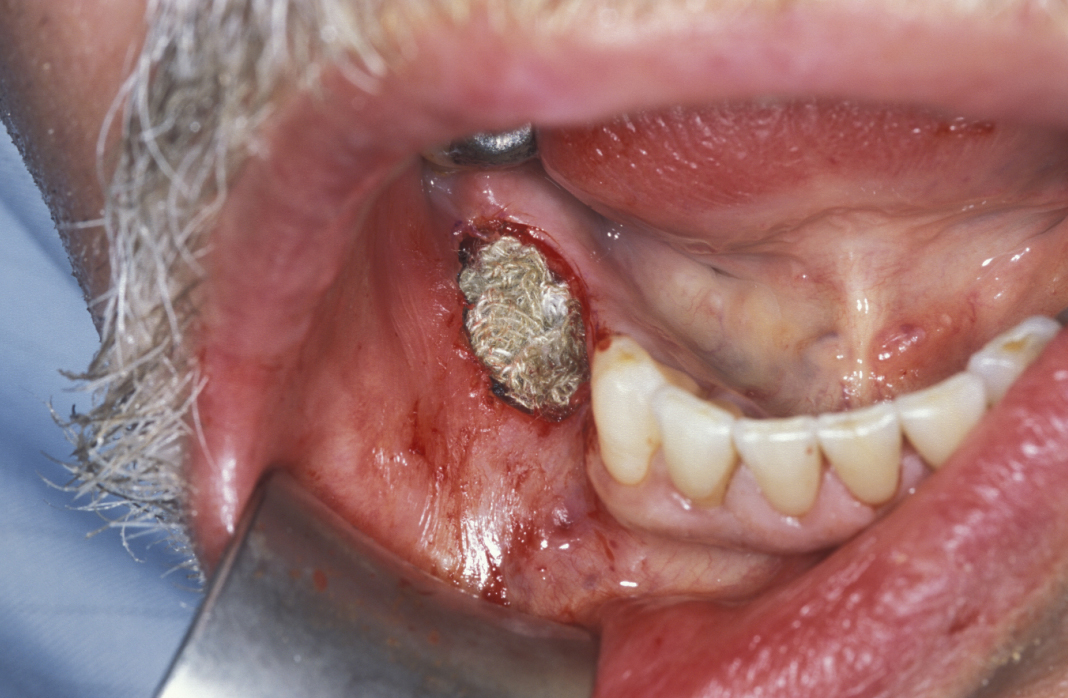

Enucleation involves the stripping away of the cyst lining from the resorbed bony cavity, resulting in a clean ‘hole’ in the bone. This deficit is filled by blood which organises into osteoid and then into new bone. There has never been an evidence-based demonstration of need to graft or fill the defect with synthetic substances. A step by step illustration of the procedure is shown in Figures 1 to 6.

Figure 1: Flap to expose bone expanded by the underlying cyst.

Figure 2: Buccal cortex (outer hard shell of bone) is removed to create a bone window for enucleation of the cyst.

Figure 3: The plane between the cyst lining and the bone cavity is bluntly dissected.

Figure 4: Teasing the cyst by direct traction and dissection delivers the cyst.